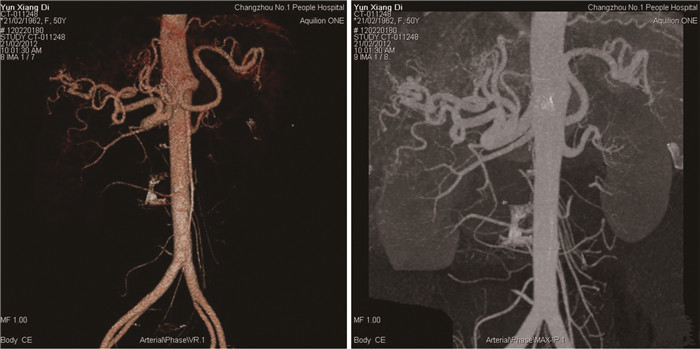

肝脏遗传性出血性毛细血管扩张症1例报告

王婷婷, 马亮, 陈建平

2022, 38(2): 423-425. DOI: 10.3969/j.issn.1001-5256.2022.02.032

摘要(1110) HTML (367) PDF (2696KB)(54)

摘要: